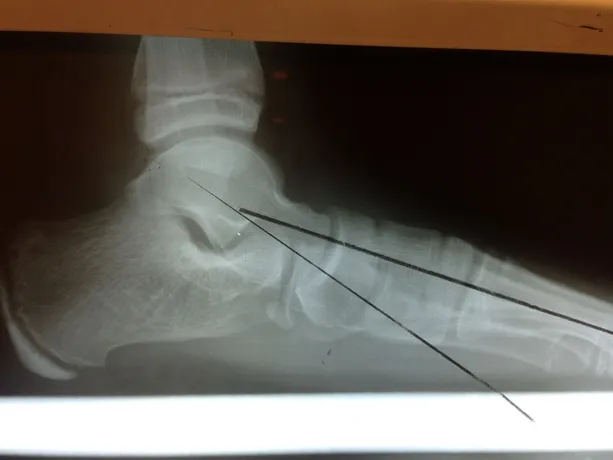

Pre and Postop X-rays Subtalar Joint Implant (Below)

Patient JD